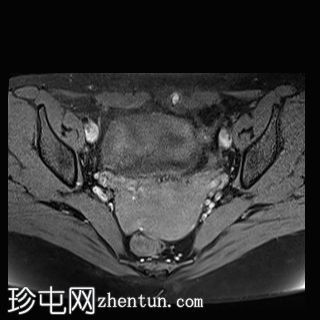

轴位

T2加权像

MRI特征符合剖宫产术后瘢痕子宫内膜异位症,表现为特征性T1高信号伴T1FS持续存在,T2低信号伴内部高信号灶,病灶边缘浸润于腹前壁肌肉内,以及对比增强。

该病灶累及腹白线并浸润腹直肌,主要位于中线左侧,耻骨联合及结节处腹直肌起点上方。

影像学表现符合病灶内出血成分,提示既往剖宫产瘢痕处存在异位子宫内膜组织。

未见明确的腹膜内或皮下软组织侵犯。

双侧卵巢增大,内含多个小卵泡(每侧卵巢10-12个或更多)。